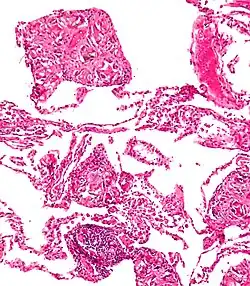

A foreign body reaction (FBR) is a typical tissue response to a foreign body within biological tissue.[1] It usually includes the formation of a foreign body granuloma.[2] Tissue encapsulation of an implant is an example, as is inflammation around a splinter.[3] Foreign body granuloma formation consists of protein adsorption, macrophages, multinucleated foreign body giant cells (macrophage fusion), fibroblasts, and angiogenesis. It has also been proposed that the mechanical property of the interface between an implant and its surrounding tissues is critical for the host response.[4][5]